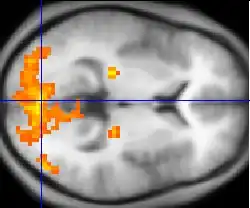

In 2012, Sorger et al. attempted to improve the previously mentioned spelling device by utilizing functional magnetic resonance imaging (fMRI).[7] The group's spelling device associated the participant's performance of certain mental tasks to a specific blood oxygenation level-dependent (BOLD) signal. BOLD signals can be used to determine which brain region activates when the participant performs a mental task.[8] The group recorded the BOLD signals for each participant for three distinct tasks: 1) motor imagery, 2) mental calculation, and 3) inner speech. The alphabet's letters were encoded with just three BOLD signals by using three task onset delays and three task durations. For example, if the patient wanted to select the letter "E", they would wait 10 seconds from the onset of the scan and then perform a motor imagery task for 30 seconds. The fMRI-based spelling device only requires about 10 to 50 seconds in order to select a specific letter of the alphabet. However, the clinical application of fMRI-based spelling devices is limited by the cost and size of MRI machines.